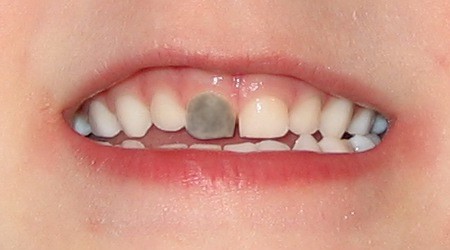

Black Teeth: Symptoms, Causes and Treatment

Black teeth can be a concern for many people; a black tooth will affect your smile and impact on your confidence. If you have a black tooth, read on to find out more about the symptoms and causes and treatments that may be available.

What causes a tooth to go black?

There are many reasons why a tooth can begin to go black, anything from simple staining to the death of the tooth can cause blackness and darkening.

The death of a tooth

When a tooth dies, the blood supply – which gives the tooth its natural, healthy color – will stop. Because the tooth is not receiving the nutrients it needs, it will begin to necrotise, darken, die and slowly go black.

Will my tooth go black after root canal?

A common misconception is that a tooth will go black after a root canal treatment. Teeth will often go black before root canal treatment as the tooth rots and decomposes on the inside. If root canal treatment is done well, all of the decomposing tissue will be removed and the blackness will not get worse. There may, however, be some mild darkening of the tooth after a root canal, depending on exactly how the root canal treatment is done and with which material.

How long does it take for a tooth to go black?

If the cause of the blackness is due to tooth decay, the blackness can happen over a period of years. If the cause of the blackness is due to trauma, as soon as the blood supply has been cut off from the tooth, the internal tooth tissue will begin to die and turn black.

Will a dead tooth go black?

If a dead tooth is left untreated, it will go black as the internal tooth tissue dies and decomposes. If the dead tooth has been root treated with a tooth-colored treatment, the tooth may not go completely black, although it may darken slightly.

Treatments for a black tooth

Black spots on teeth can be treated quite simply, these can often be caused by a small pit or chip in the tooth which either picks up staining or has a small amount of decay. Your dentist can usually remove a small amount of tooth around this area, removing the staining and/or decay and placing a some tooth-colored bonding material over this area. The tooth bonding will blend in naturally with your surrounding teeth, making the repair invisible.

Dead tooth whitening is also possible. This is whitening with a peroxide gel which can whiten teeth significantly; however, sometimes teeth whitening alone is not enough to whiten a dead tooth and some form of restorative option needs to be considered, either a dental veneer or a dental crown.